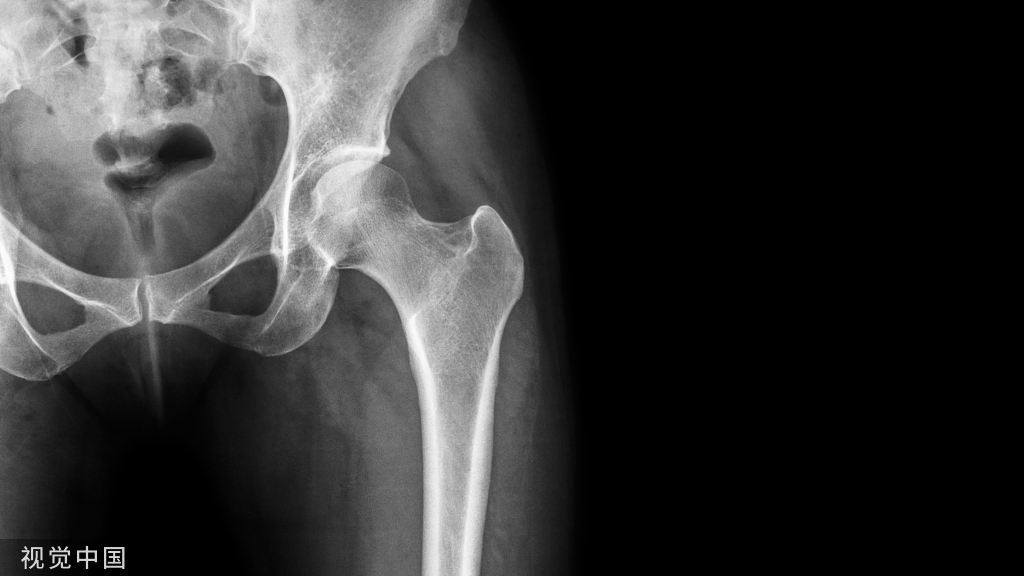

骨质疏松症( osteoporosis,OP) 是最常见的骨骼疾病,是一种以骨量低,骨组织微结构损坏,导致骨脆性增加,易发生骨折为特征的全身性骨病。

一旦骨质严重流失,骨骼的内部结构将变得脆弱,距离骨质疏松就越来越近,骨头的质量和力量都被削弱,很容易导致突然和意外的骨折,也就是我们通常所说的“骨脆脆”。

骨质疏松性骨折,多见于老年女性,特别会发生在腰椎及胸椎,即出现锥体压缩性骨折,这是老年性骨质疏松症最常见和最严重的并发症。